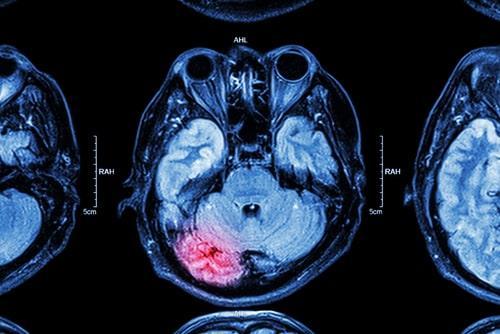

A traumatic brain injury or TBI involves damage to brain tissue resulting from a blow to the head or a strong jolt to the body that causes the brain to move around inside the skull. This may result in bruising of the brain, torn brain tissue, or serious bleeding, which can put pressure on the brain and cause additional damage. A mild traumatic brain injury may result in symptoms such as headaches, nausea, vomiting, fatigue, dizziness, blurred vision, ringing in the ears, confusion, temporary memory loss, or loss of consciousness. These symptoms will usually last for a short period of time, typically around a few days to a week.

Multiple forms of medical treatment may be needed to address moderate or severe traumatic brain injuries. Surgery may be required to remove blood clots or dead brain tissue and relieve pressure on the brain. A person may need to take medications such as anticoagulants to prevent blood clots, anticonvulsants to address seizures, muscle relaxants to address muscle spasms, or antidepressants to treat mood disorders. Multiple forms of ongoing rehabilitative therapy may also be needed, such as physical therapy, speech therapy, psychological treatment, or occupational therapy.